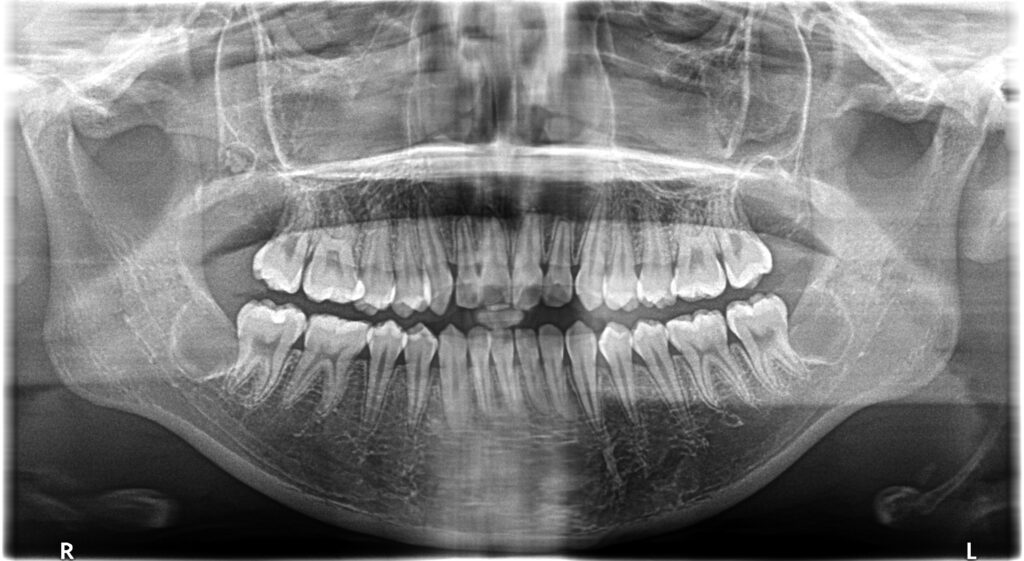

• 初診:2012年、9歳女児、

• 主訴:出っ歯と歯のがたがたが気になる。

• 診断:1級過蓋咬合、上下前歯叢生、上顎左右側切歯クロスバイト

• 治療方針:非抜歯で行う。虫歯予防(フッ素)、歯磨き指導、上下拡大床→最小限のデイスキング→マウスピース矯正→下親知らずの抜歯、保定→メンテナンス